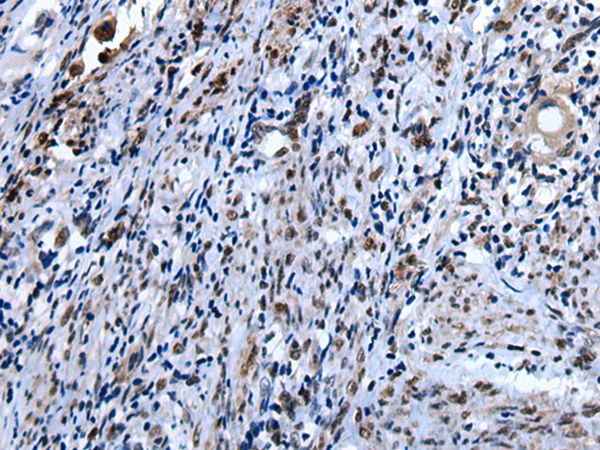

IHC positive control: |

Human colorectal cancer and human cervical cancer |